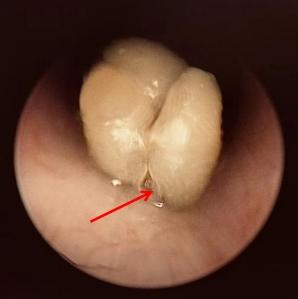

手術期間,醫生更發現,由於氣管環境溫暖、潮濕,黃皮核已經發芽、膨脹,大大增加取出難度。經過一場「拉鋸戰」,這顆發芽黃皮核終於從小周氣管內安全拔出。